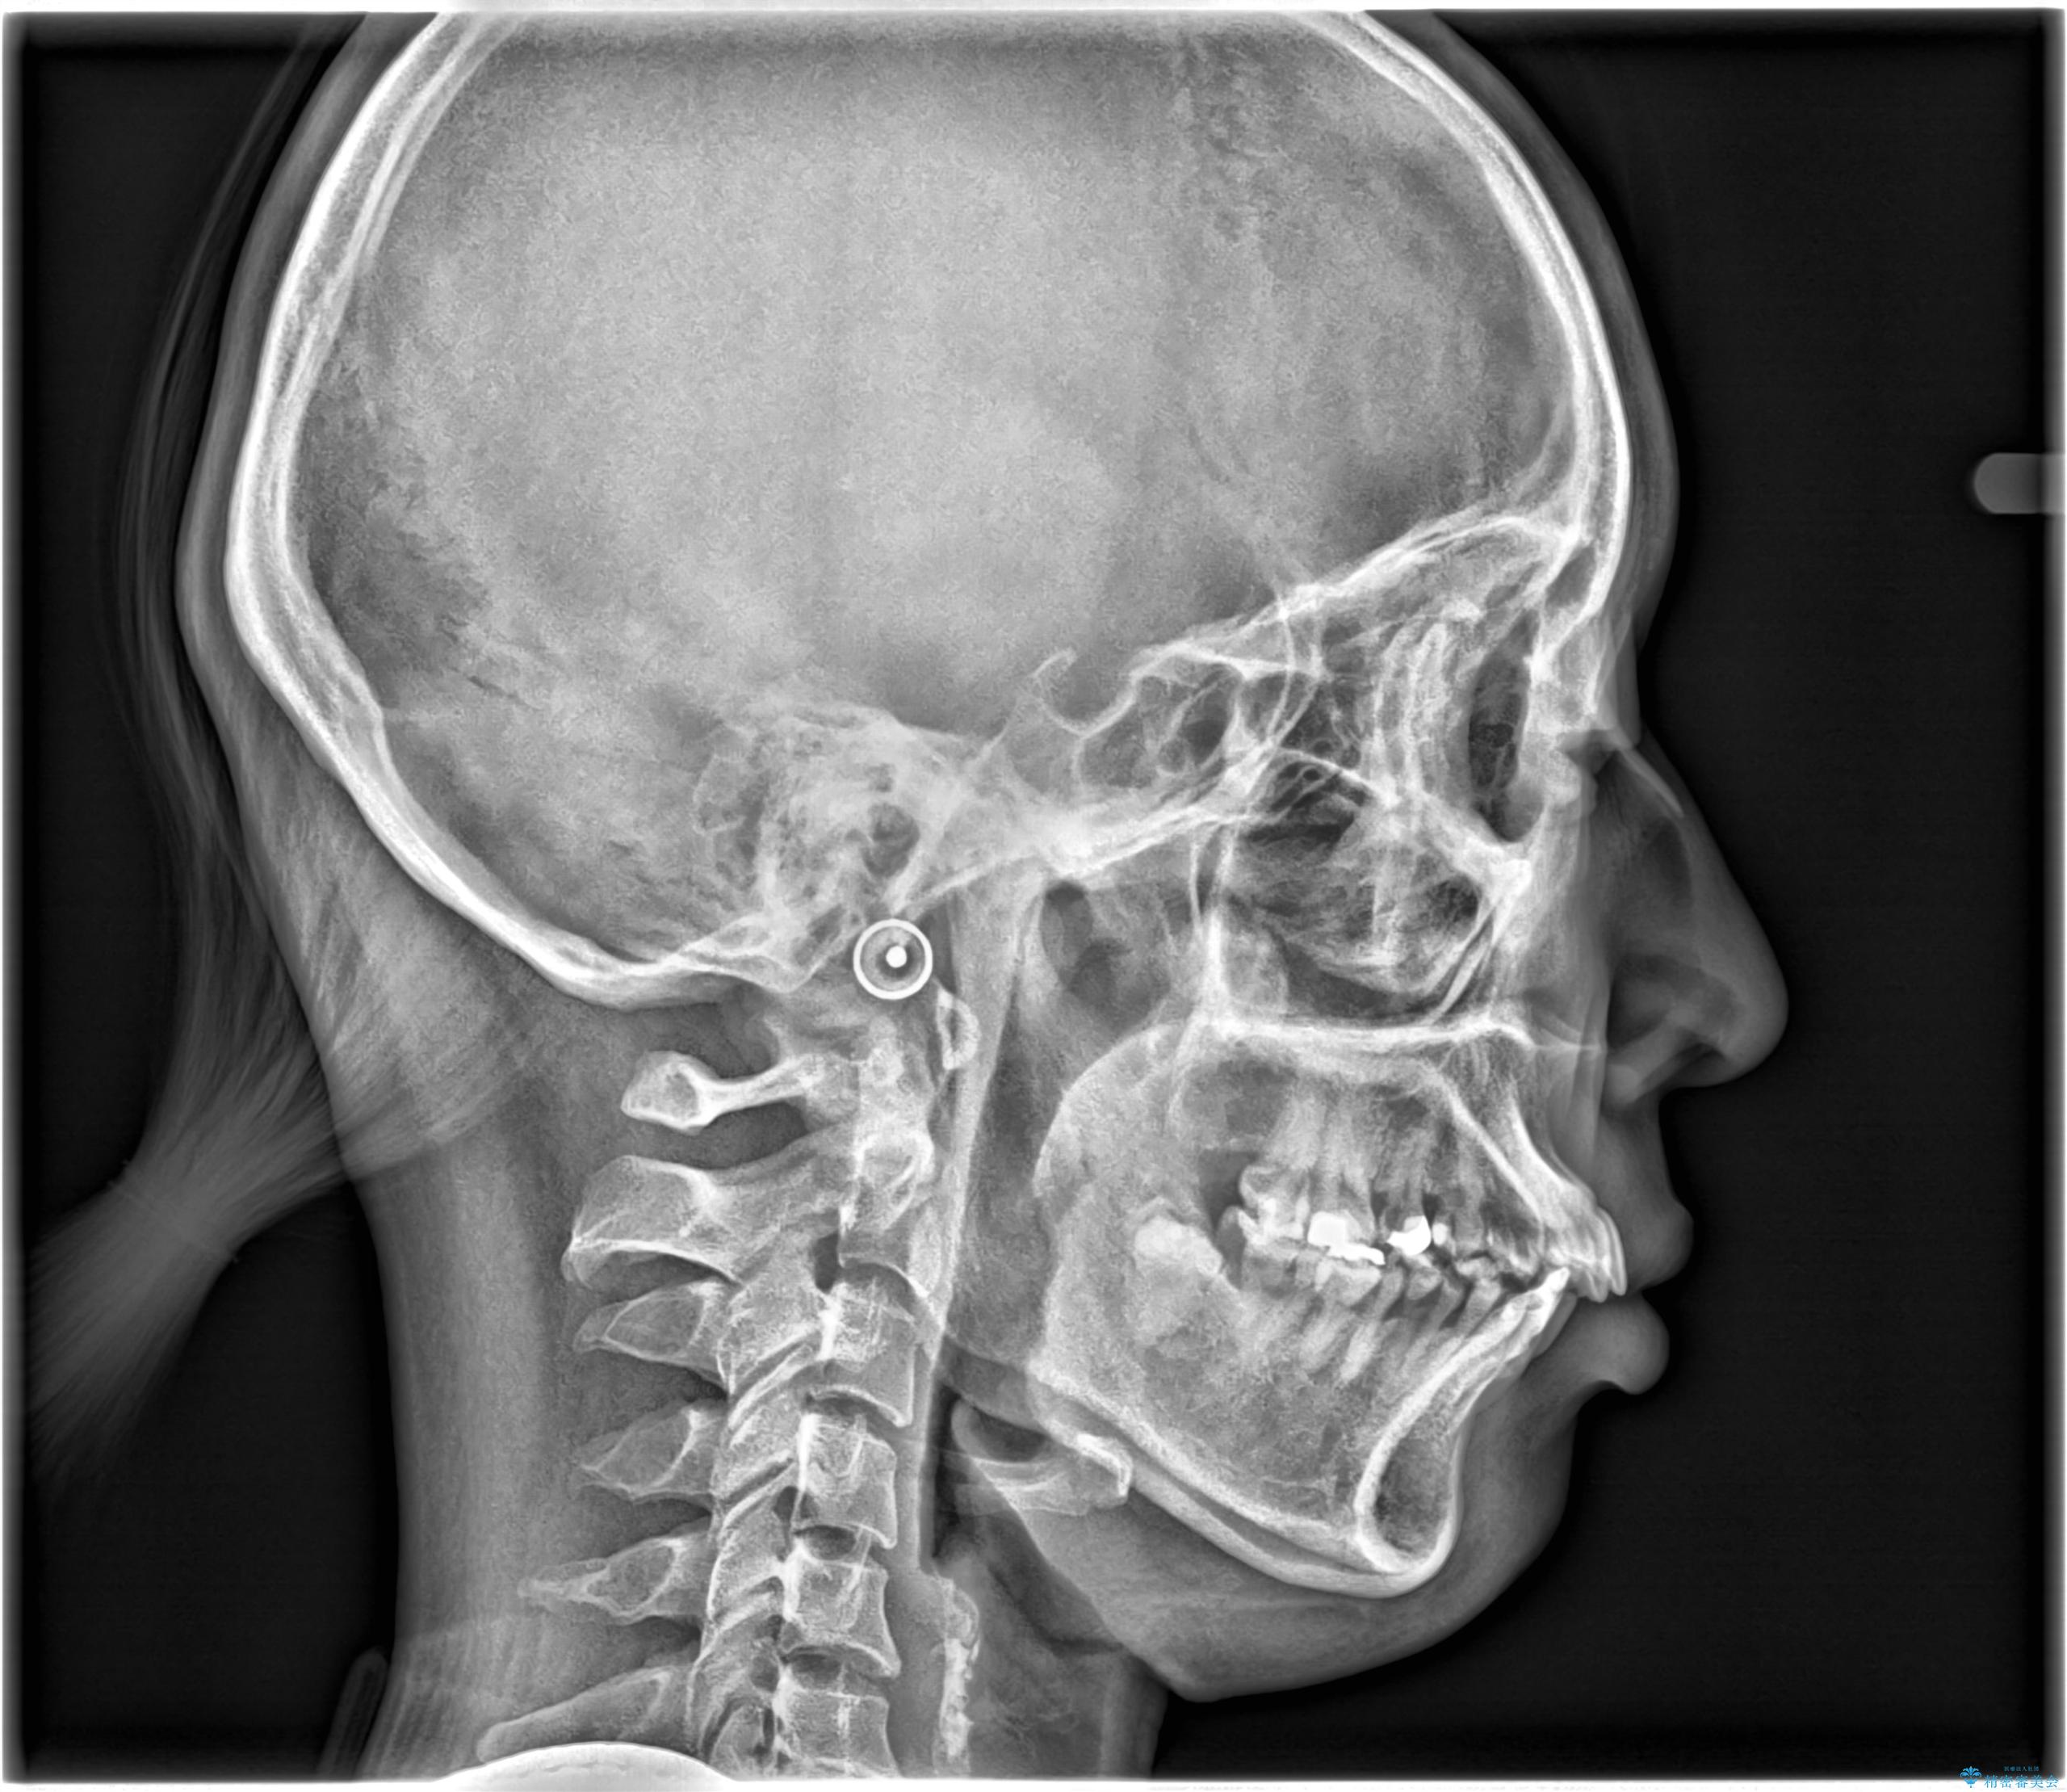

- 主訴:学生時代に矯正治療したが、後戻りしてしまった。上下前がのガタつきを治したい。

ワイヤー矯正(審美装置)非抜歯 治療期間:1年8か月

途中、大臼歯の遠心移動のためリンガルアーチを使用しています。